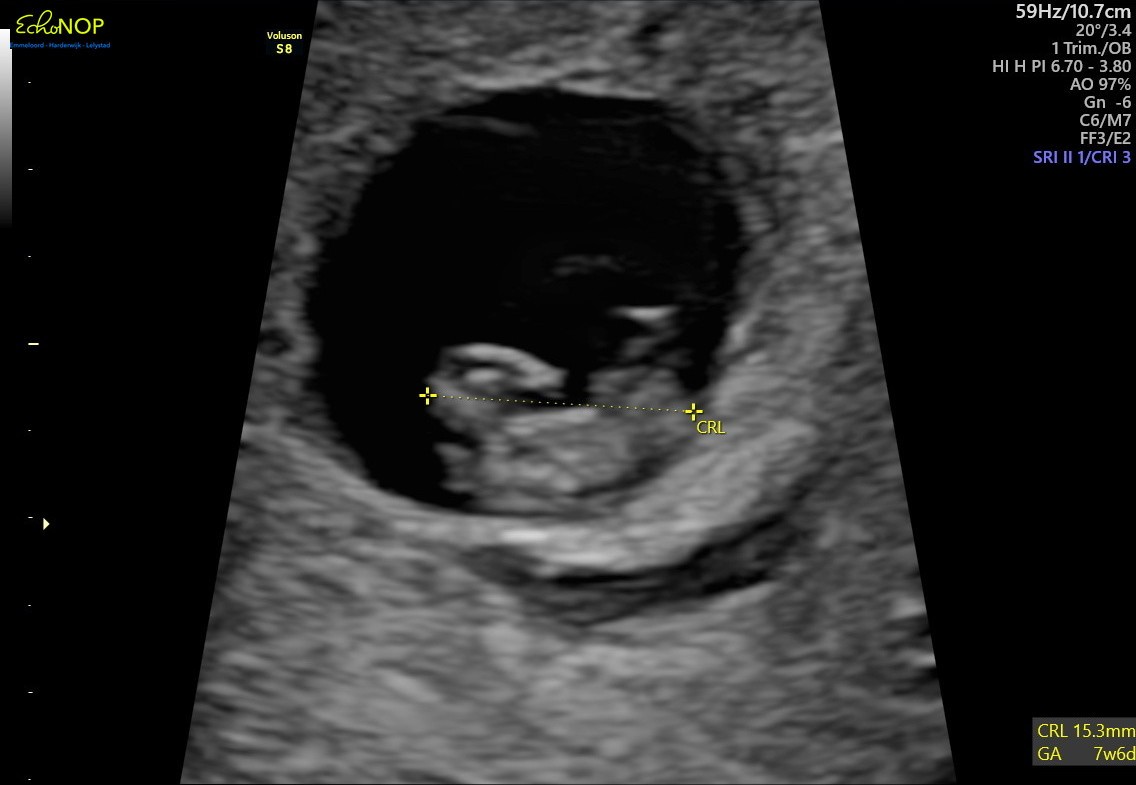

Jesteśmy od kilku dni w PL i ogarniam powoli temat lekarza. Wiadomo jak to teraz wygląda przez koronaświrusa. Nie spieszę się bo termin wypada gdzieś na 29.08, om 22.11, zatem mamy dopiero 6+3 dni i jeszcze dużo przed nami.